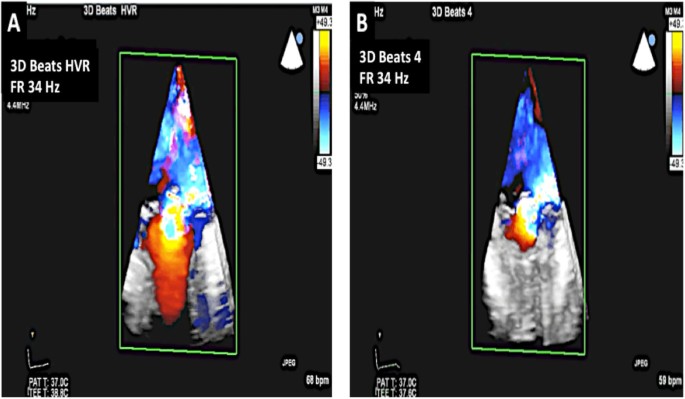

3D color and assessment of MR. A: In HVR mode, the location of the regurgitant jet can be identified. Also note the frame rate of 34 Hz. B: A 4 beat 3D acquisition can also be undertaken which gives a frame rate of 34 Hz. However, in the presence of arrhythmia, localization of the regurgitant jet may not be possible due to significant stitch artifact.